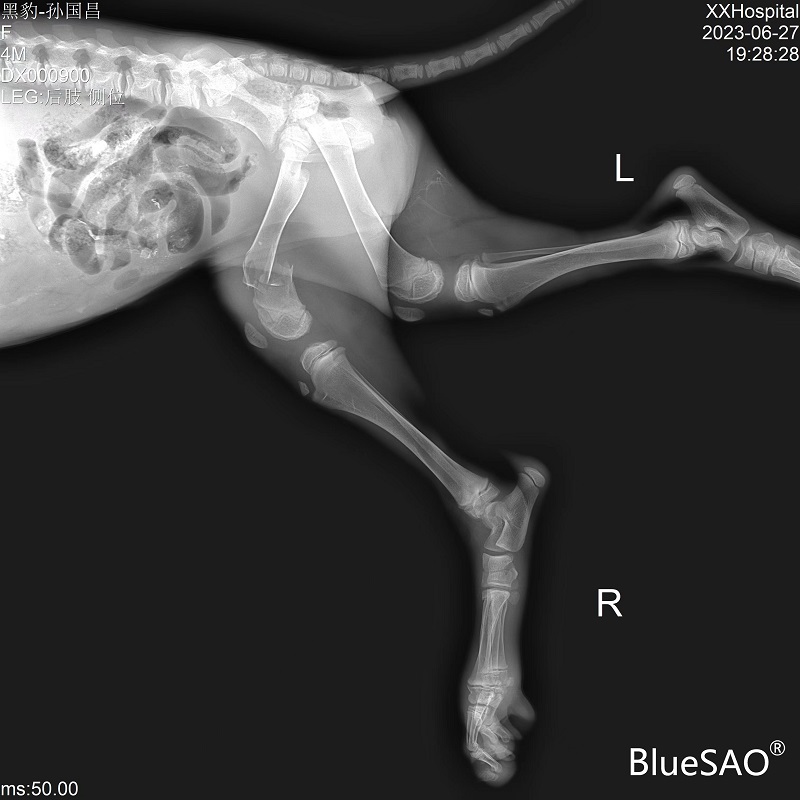

德牧犬,2.5个月,雌性,体重5Kg。车祸导致股骨远端骨折,术中使用BlueSAO佰陆PRCL®-8.5mm纯钛锁定骨板进行内侧及外侧固定。复位良好,望早日康复!